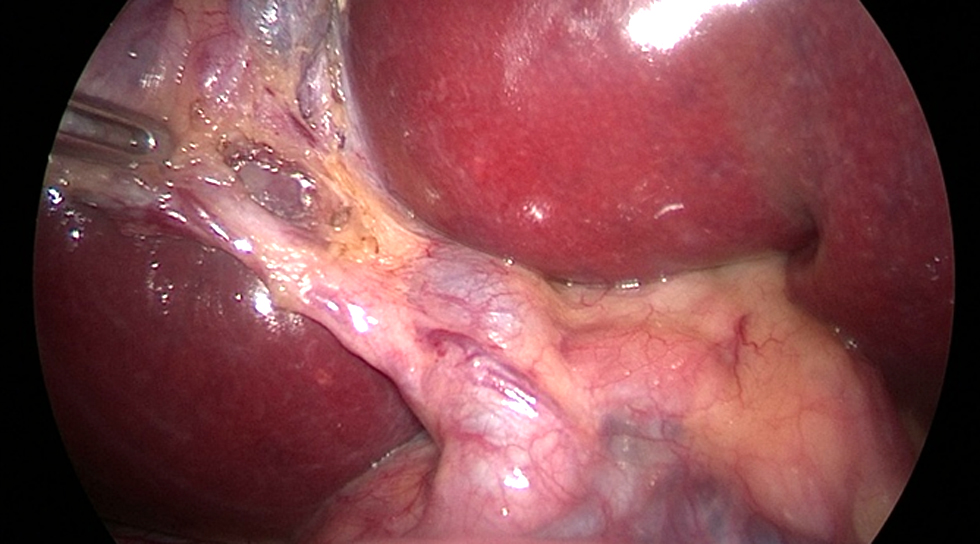

The supra-umbilical open procedure (Hasson's technique) was used to achieve pneumoperitoneum. LC made the four standard tiny incisions in the abdominal wall to introduce two 5 mm and two 10 mm diameter operating ports. Through those ports, the surgical instruments and telescope were inserted into the peritoneal cavity. In our study, the extrahepatic biliary tree was delineated using two cholangiography techniques: urografin and ICG. We'll go over both strategies in detail. The supra-umbilical port was observed with a 10 mm telescope. The surgeon used a second 10 mm port, his right working port, in the epigastric area. A 5 mm port in the right hypochondrial region served as the surgeon's left operating port, while another 5 mm port in the right lumbar region was employed for the traction of the gallbladder fundus. With the left hand, retracting Hartmann's pouch, while the right hand performed anterior and posterior dissection in Calot's triangle, creating a large window. A critical perspective on safety is crucial in preventing injuries to right hepatic artery or bile duct (fig. 1). To separate the gallbladder from its bed, the cystic duct and artery were cleaned, dissected, controlled with clips, and finally severed. The gallbladder was extracted through the epigastric port with closure of ports openings.

Figure 1 - Critical view of safety showing cystic duct, cystic artery & CBD.